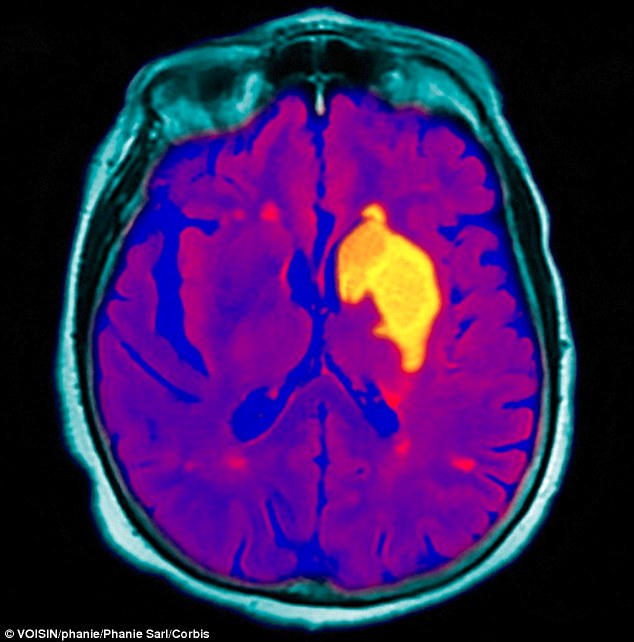

الأمراض الدماغية الوعائية

أي الأمراض التي تؤثر على أوعية الدماغ، وهي من أهم المشكلات الصحية، نظراً لشيوعها وتأثيرها الكبير على حياة الفرد.  والمقصود به عموماً حدوث فقدان مفاجئ لوظيفة جزء من الدماغ أو أجزاء. وتقدر منظمة الصحة العالمية أن أكثر من 17.5 مليون شخص لقوا حتفهم من أمراض القلب والأوعية الدموية مثل أزمة قلبية أو جلطة في عام 2012. ومفتاح الوقاية من هذا المرض هو اتباع نظام غذائي صحي وممارسة النشاط الرياضي بانتظام، وعدم استخدام منتجات التبغ.